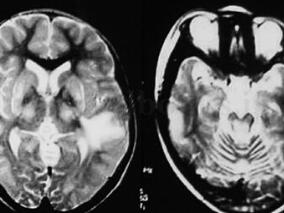

1小时条评论【病例资料】 患者,女性,40岁,北京市干部。因四肢麻木、无力2个月余于1995年7月18日收入院。 现病史:患者于1995年5月无明显原因发热,体温约38.5℃,按上呼吸道感染治疗后体温恢复正常。2周后出现四肢麻木、无力,无明显疼痛,于外院就诊,诊断为周围神经病变...